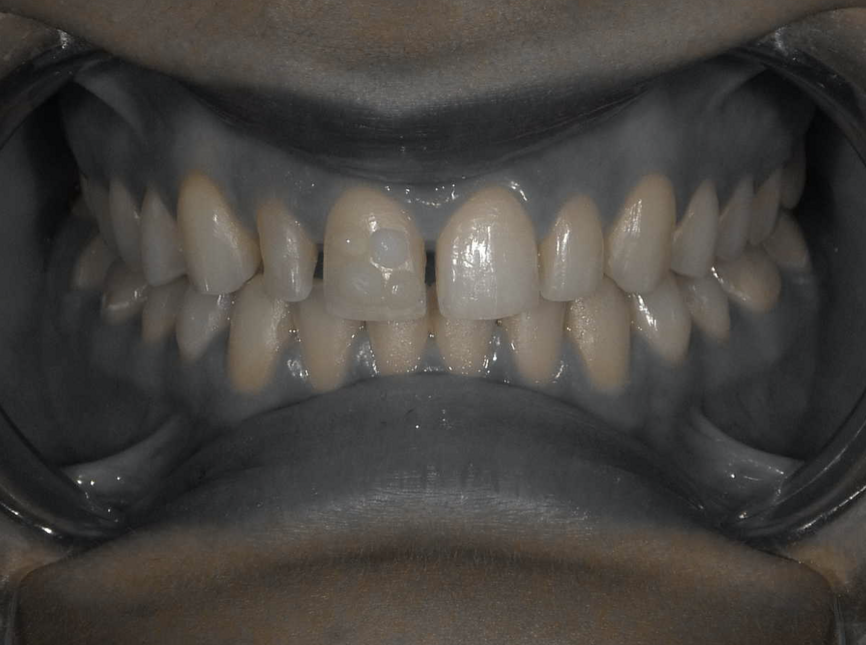

A young female patient visited the clinic requesting for an enhanced smile as she was unhappy with the appearance of her front teeth after completing orthodontic treatment. Upon careful examination it was observed that composite resin restorations were used for diastema closure before orthodontic treatment (Fig 1, 2). The filled teeth had chipped at the incisal edge and had a grey discolouration. After careful evaluation the following treatment options were suggested to the patient:

Fig 2: Pre-operative retracted view